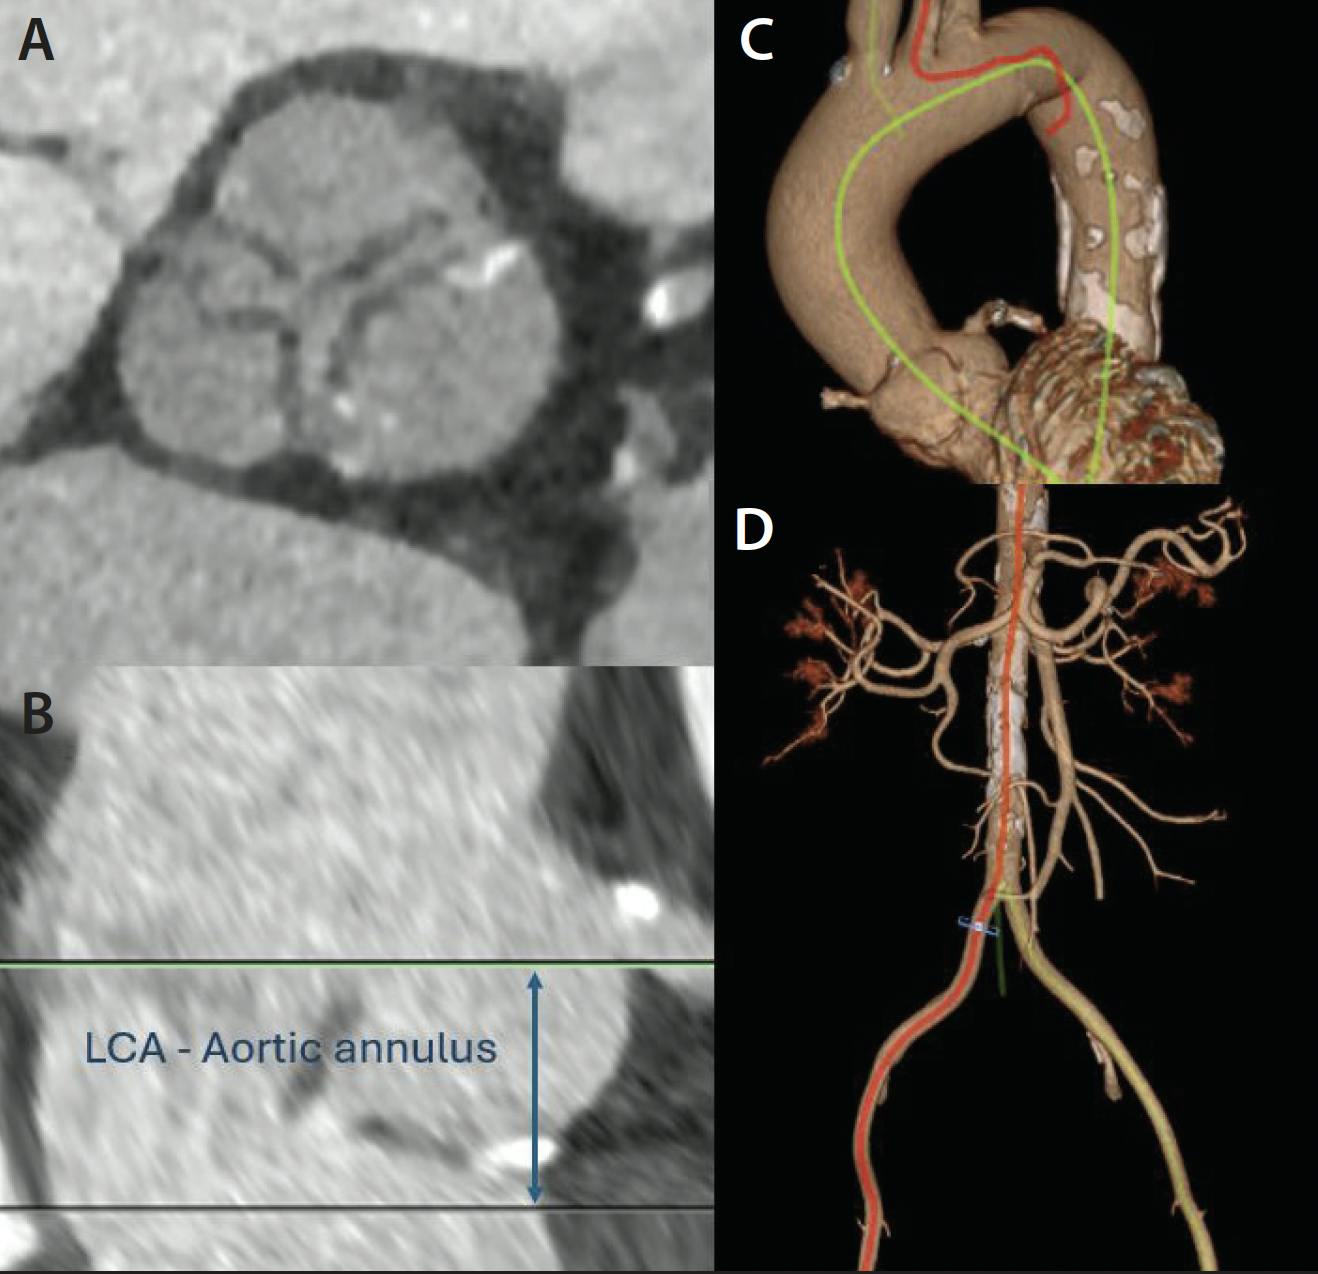

CT is a valuable tool in the preoperative assessment of patients with AR, providing comprehensive anatomic information about valvular type, presence and pattern of calcification, and evaluation of aorta morphology (Figure 4). The following measurements and imaging features are essential for ensuring accurate valve sizing and optimal prosthesis deployment, as well as minimizing peri- and postprocedural complications17:

1. Aortic annulus dimensions: Annular perimeter and area are critical for selecting the appropriate valve size.

2. Aortic root and ascending aorta: Measurements of the sinus of Valsalva, sinotubular junction, and ascending aorta are essential to ensure proper valve fit and avoid complications such as coronary obstruction.

3. Valve morphology: Assessments of the aortic valve morphology and AR mechanism are important for deployment. Bicuspid aortic valve is a contraindication for current dedicated AR devices.

4. Coronary ostial heights: The distance from the aortic annulus to the coronary ostia must be measured to prevent coronary obstruction during valve deployment.

5. Membranous septum length: This can contribute to increased risk for pacemaker.

6. Aortoiliofemoral system: This is useful for determine the best vascular access route and identifying potential tortuosity, calcification, or pathologies that could cause problems with advancement of the delivery system.

Figure 4. Comprehensive assessment for TAVR. The evaluation of valve anatomy and morphology (A). The assessment of coronary ostial height (B). The assessment of aortic root and ascending aorta (C). The evaluation of vascular access route (D). LCA, left coronary artery.